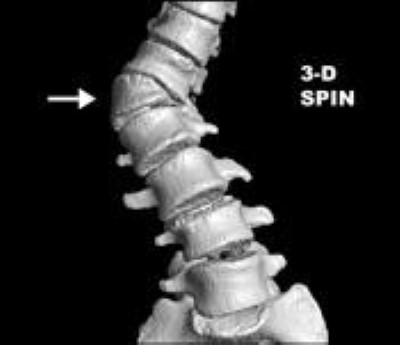

Computed tomography (CT) scan. A CT scan can provide a detailed image of your child's spine, showing the size, shape, and position of the vertebrae. To see the vertebrae better, your doctor may have a 3-D image made from the CT scan. This looks like a photograph of the bones.

CT scan shows hemivertebrae, as well as a fused, boney block

This 3-D image from a CT scan shows hemivertebrae, as well as a fused, boney block.

Courtesy of Scottish Rite for Children, Dallas

CT scan of hemivertebra in congenital scoliosis

A single hemivertebra in the lower back shown in a 3-D image from a computed tomography (CT) scan. Note the four normal rectangular vertebra below the single triangular-shaped hemivertebra (arrow). This wedged vertebra creates the deformity that would not have otherwise been there.